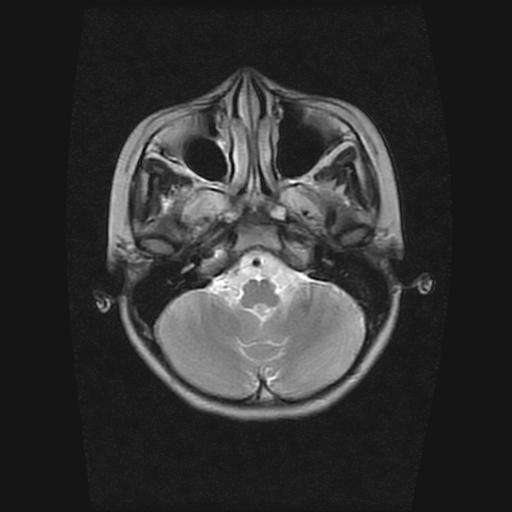

9岁女孩,三岁时诊断为癫痫,一直服丙戊酸钠,现患者一般情况良好,家长复查核磁片,看能否停药..

巨脑回

未见异常信号灶.

未发现异常信号。

停药要结合临床,如无发作可以停。